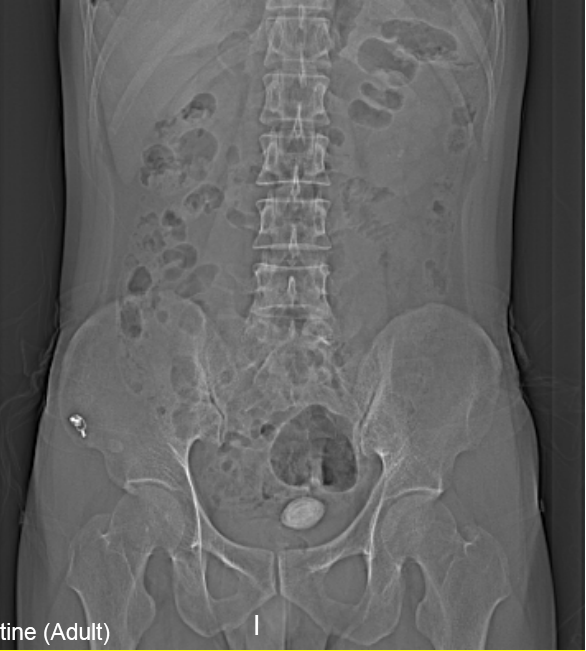

“醫(yī)生我尿不出,尿里有血,快幫幫我”。近日,在溫州市人民醫(yī)院泌尿外科門診一位男青年向坐診的黃來(lái)劍主任求助,經(jīng)驗(yàn)豐富的黃主任在了解基本病情后,特意觸摸了一下患者恥骨上區(qū),并囑咐患者進(jìn)行泌尿系平片檢查,結(jié)果在意料之中也出乎意料之外。意料之中的是患者診斷如黃主任所想膀胱結(jié)石進(jìn)入尿道卡住了,意料之外的是結(jié)石直徑達(dá)到了35mm,像蛋黃大小了,這對(duì)年輕患者來(lái)說(shuō)并不常見(jiàn),堵住了尿道,把患者痛的夠嗆。

▲患者影像學(xué)檢查